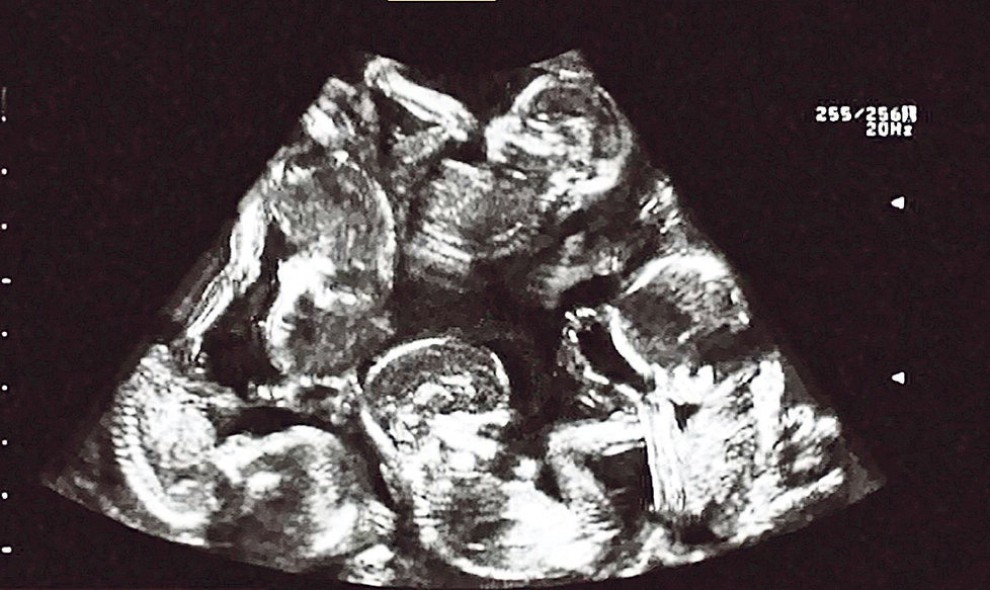

A lo largo de una consulta con el ginecólogo, el médico empezó con el ultrasonido y fue ahí cuando supieron la enorme noticia; no unicamente se había logrado concebir a un niño recién nacido, sino que ahí dentro del vientre de Guillermina había 5 corazoncitos que latían con fuerza.

Tanto la pareja como los doctores deseaban sostener el embarazo el más grande tiempo viable para que los 5 pequeñines lograran realizarse lo más bien que se pueda y no hubieran adversidades a lo largo de el parto.

Los 5 niños recién nacidos nacieron en perfectas condiciones, pensando cerca de 900 gramos y 1.4 kilos, debido al enorme conjunto de doctores que fueron el parto.Durante una rueda de prensa la médico responsable Elizabeth O’Brien ratificó que los niños recién nacidos habían nacido con triunfo y que “fue increíble ver lo bien ordenado que se encontraba el equipo”, ya que en la salón había cerca de 8 doctores, 12 enfermeros y 1 anestesista, quienes lograron sostener tranquila a Guillermina y a los niños recién nacidos en todo instante.